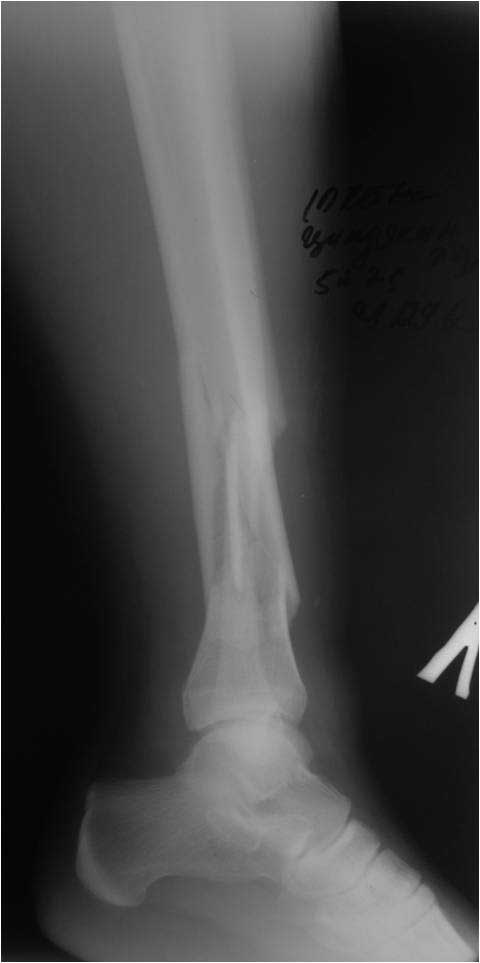

[Ortho] Деформация фиксатора после падения

первичные снимки и остальные качеством получше.

Имя     : 123.jpg

Имя     : lat.jpg

Имя     : AP.jpg

Имя     : AP2.jpg

Имя     : 1231.jpg